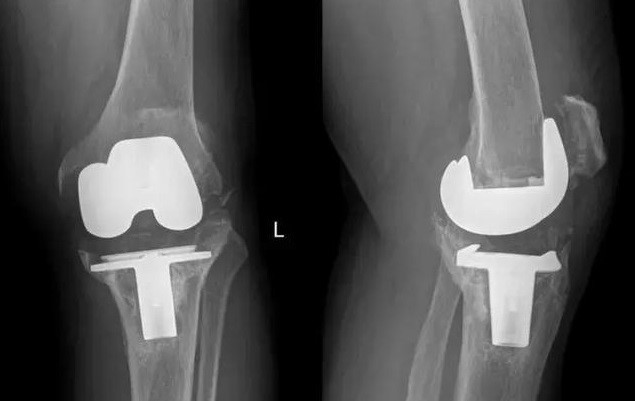

2017年11月,我國完成了全球首例個性化3D打印鉭金屬墊塊植入的全膝關(guān)節(jié)翻修手術(shù);2018年,LPW科技公司與環(huán)球先進金屬集團有限公司(GAM)宣布達成合作協(xié)議,圍繞金屬鉭的增材制造技術(shù)可為醫(yī)療外科、牙科、軍事、航空航天以及其他市場領(lǐng)域提供服務(wù)。鉭金屬通過3D打印制成的多孔鉭植入體,相較常見的多孔鈦植入物,具有更好的生物力學(xué)適配性、并具有接近人骨的彈性模量。在植入穩(wěn)定性上,具有較大優(yōu)勢。